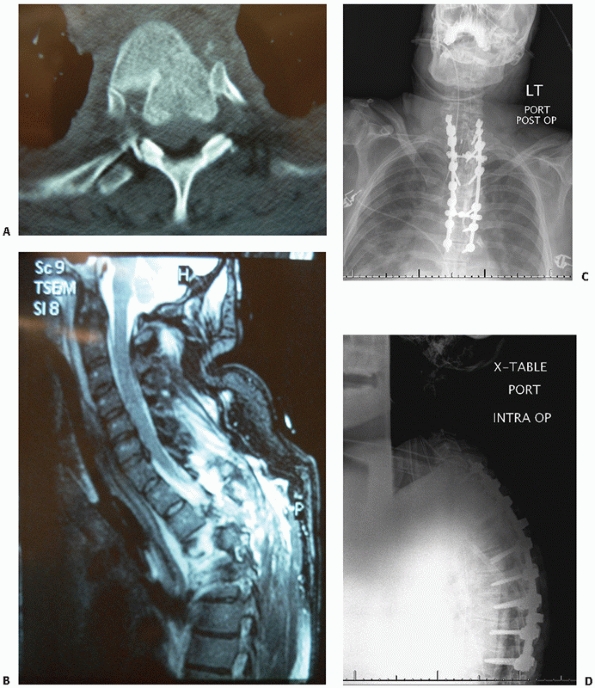

![]() |

FIGURE 43-20 Sagittal (A) and axial (B)

computed tomography images demonstrating an L1 burst injury with evidence of significant vertebral body collapse and retropulsion of fracture fragments into the spinal canal. Postoperative lateral radiograph (C) and axial computed tomography image (D) obtained following a circumferential procedure consisting of an L1 corpectomy with reconstruction using an expandable cage and anterior instrumentation followed by the insertion of short-segment posterior fixation. |